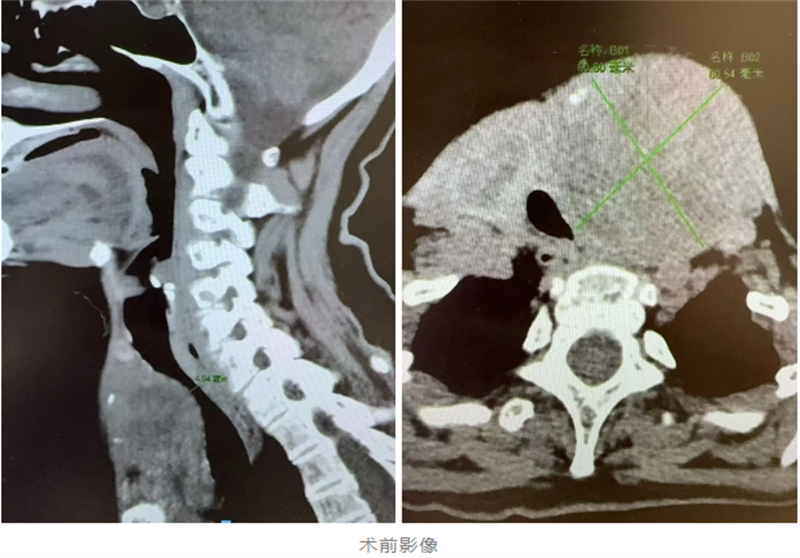

會診室內氣氛凝重而專注,專家們仔細分析著每一份檢查報告和影像資料。放射科、麻醉科、腫瘤內科專家團隊結合病例提出“患者腫瘤與氣管間隙不清,麻醉風險高、患者預期生存周期不到6-12個月,手術無法根治,內科治療效果不確切”等現實的困難。

這場手術是對技術與意志的雙重考驗。麻醉科醫生在術前反復研究患者的頸部CT,多次預演插管細節,最終在可視喉鏡的引導下,將導管精準插入被腫瘤壓迫到僅剩約35%面積的氣管里,為手術的順利完成奠定了堅實的基礎。